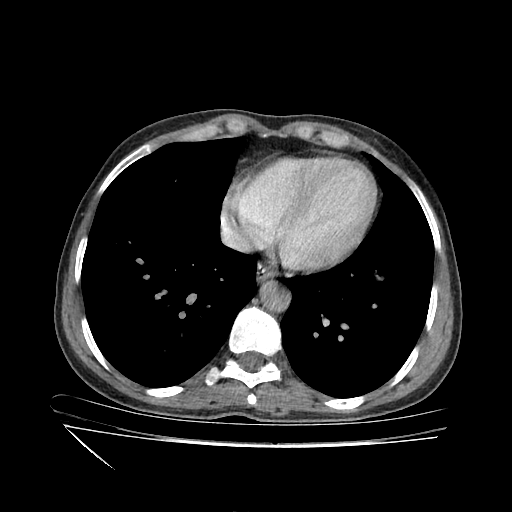

Image Grid

4×3 grid: Rows show different image types (Original NATIVE, Reconstructed NATIVE, Original VENOUS, Generated VENOUS), Columns show windowing techniques (No Window, Lung Window, Mediastinum Window)

Original VENOUS CT scan

No window - Raw intensity values

Generated VENOUS CT scan (A→B translation)

No window - Raw intensity values

Windowing Parameters

- No Window: Raw intensity values without windowing

- Lung Window: WL -600, WW 1500 → Low −1350, High +150 (optimal for pulmonary structures)

- Mediastinum Window: WL 40, WW 400 → Low −160, High +240 (optimal for soft tissues)